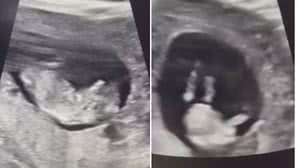

Obstetra mostra o que acontece com o bebê quando a mãe tosse e vídeo viraliza; assista